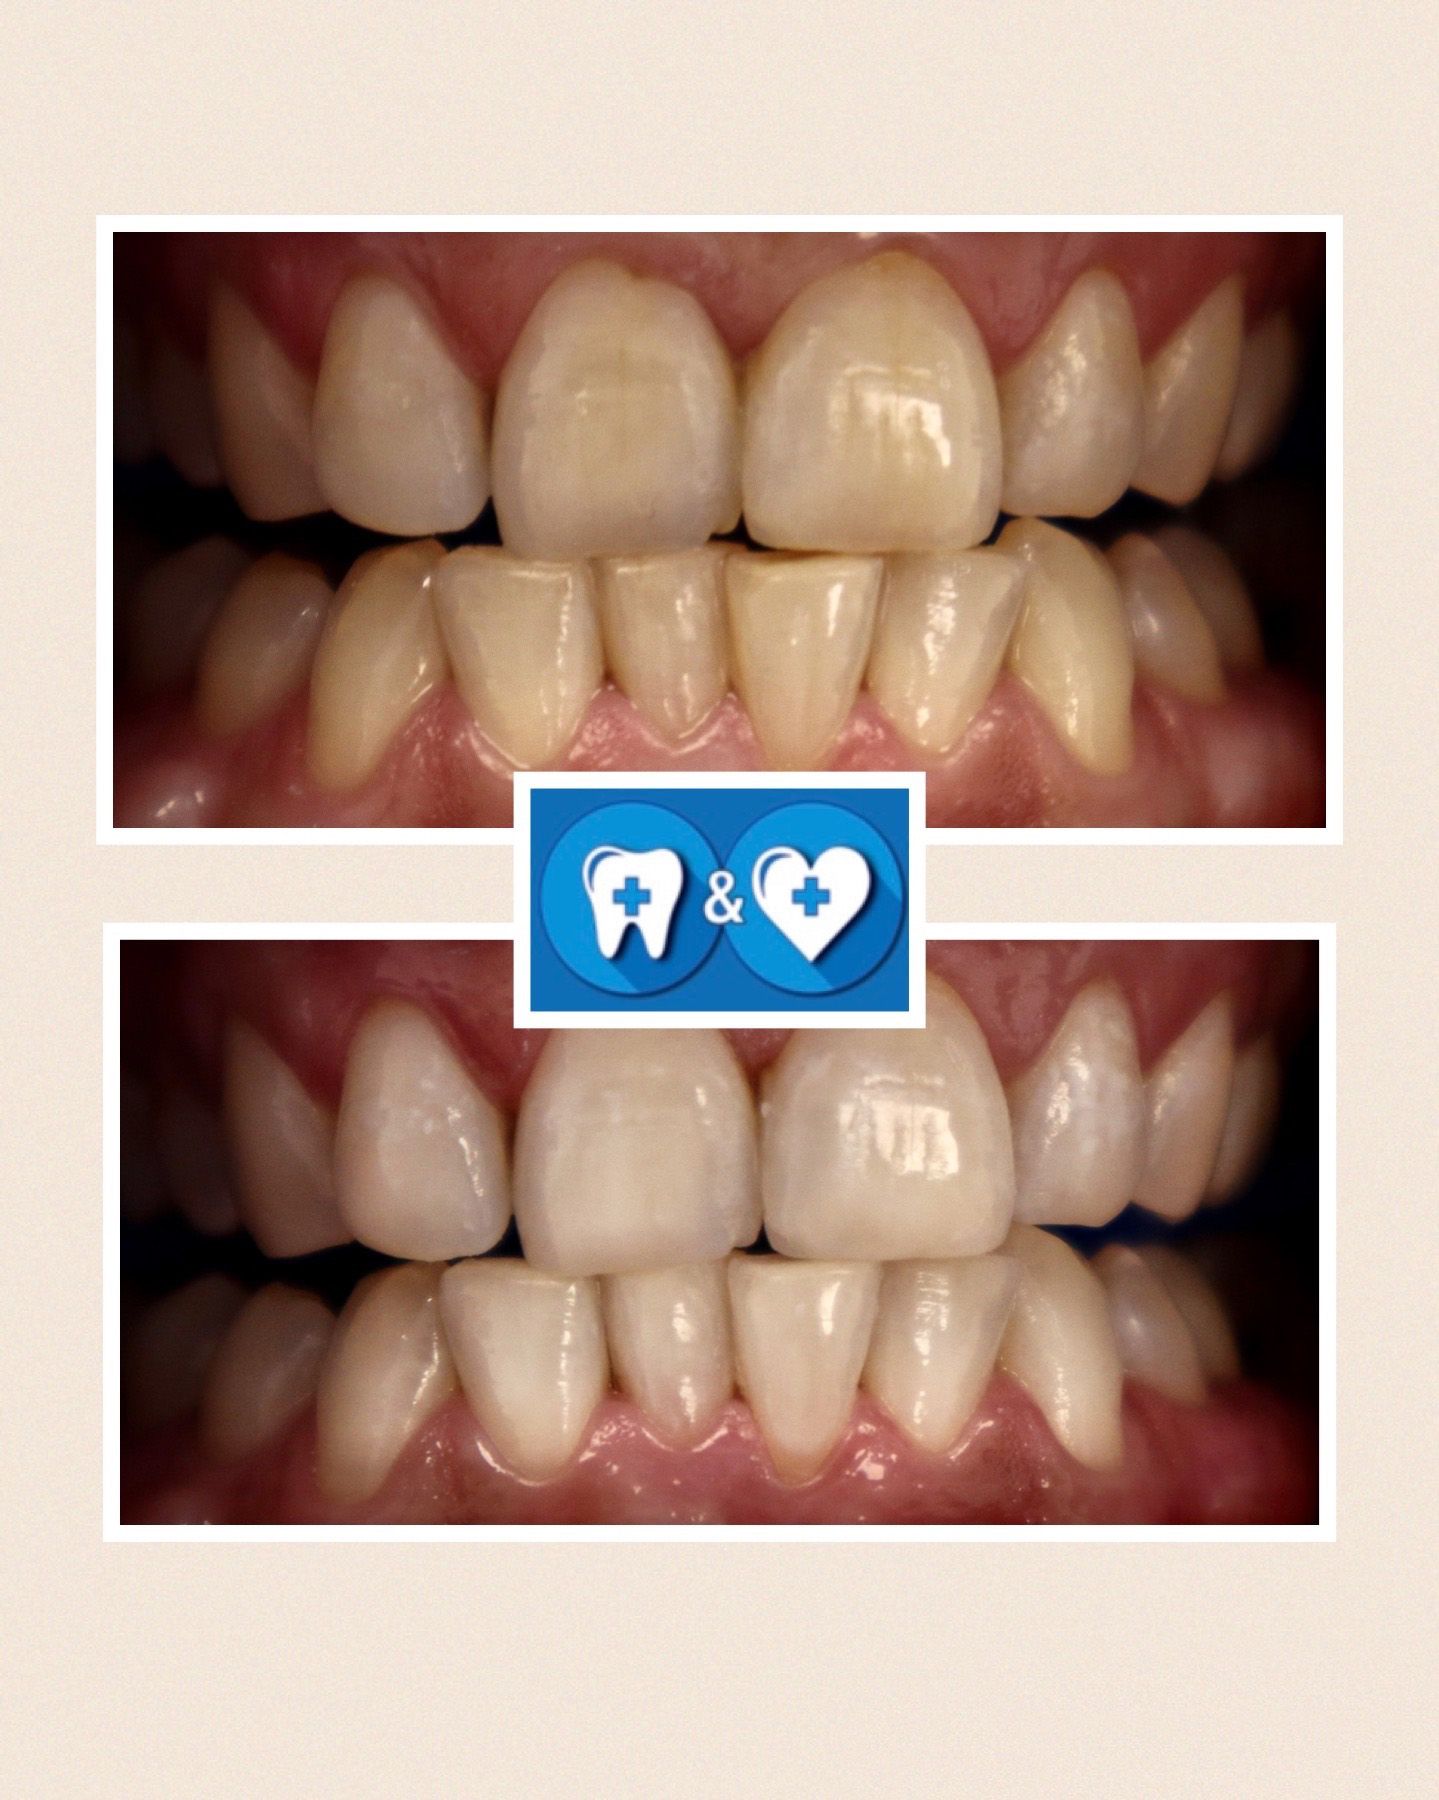

Specialiais instrumentais ir ultragarsiniu skaleriu pašaliname ant dantų susikaupusius akmenis. Su smėliasrove ir perlų soda nuvalome tabako, arbatos, kavos, vyno apnašas.

Dantų poliravimas su soda, E-FLOW technologija leidžia pašalinti atsiradusias pigmentines dėmes!

Po burnos higienos procedūros dantys bus daug gražesni ir baltesni! Ir sveikesni!